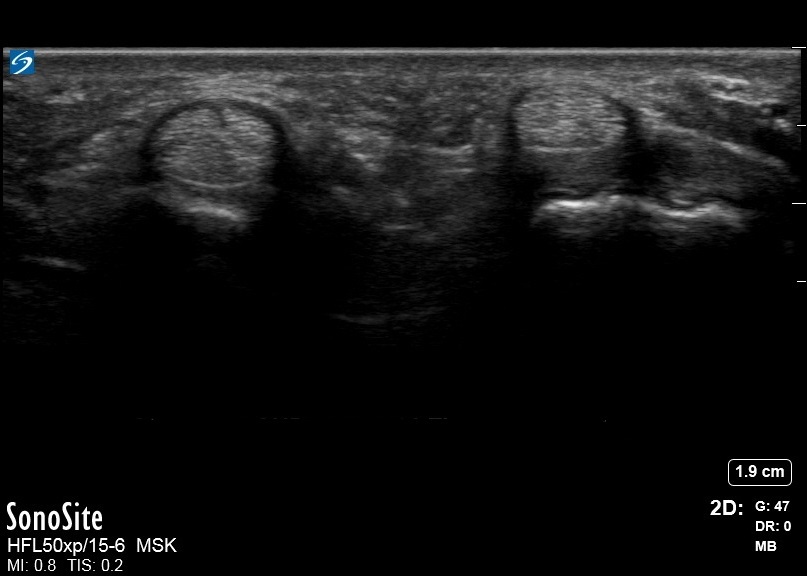

手部正常 A1 滑车图像